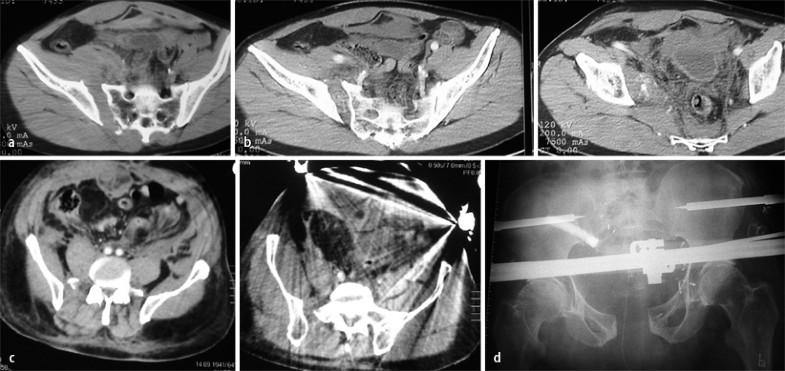

Hochgradig instabile Beckenringverletzungen (meist C-Verletzungen) gehen häufig mit lebensbedrohlichen massiven Blutungen aus den Venenplexus und/oder den Ästen der A. iliaca interna einher. Die i.v. kontrastmittelverstärkte CT bietet eine verlässliche Möglichkeit, frühzeitig relevante Blutungen zu detektieren (Fall 4, Abb. 4).

Wenngleich die Wertigkeit dieses Verfahrens insoweit umstritten ist, ob eine Leckage spezifisch für eine lebensbedrohliche Blutung im Beckenbereich ist oder prinzipiell bei jeder signifikanten Beckenringverletzung auftritt [13], bestechen doch die Spezifität (kein Kontrastmittelaustritt im Kontrastmittel-CT: keine relevante Blutung) und der negative prädiktive Wert (konsekutiv keine Angiographie/Embolisation erforderlich) dieses Verfahrens [20]. Eine Angiographie und eventuelle Embolisation stehen im Übrigen nicht an primärer Stelle der Verfahrenswahl bei der signifikanten pelvinen Blutung mit Kreislaufinstabilität, sondern die Anlage einer Beckenzwinge und/oder eines Beckenfixateurs [13]. Reicht dies zur Beherrschung der Blutung durch Kompression und Limitierung des intrapelvinen Raums nicht aus, ist abzuwägen, ob eine extraperitoneale Tamponade („packing“) oder eine angiographische Embolisation an dieser Stelle zu bevorzugen sind (Abb. 4). Das entsprechende Nofallzeitmanagement – sicherlich auch die Frage, ob zum betreffenden Zeitpunkt ein in der interventionellen Angiographie erfahrener Operateur zur Verfügung steht – ist für die Prognose des Patienten entscheidend.

Fall 4, 62-Jähriger mit AO-Verletzung 61C1.2, a,b Kontrastmittel-CT: Nachweis einer erheblichen aktiven Blutung extraperitoneal, c,d Kontrastmittel-CT: Nachweis der trotz Beckenzwinge und Fixateur-externe-Anlage persistierenden Blutung, Embolisation der aktiv blutenden A.-iliaca-interna-Äste, weitere Erläuterungen s. Kasuistik

Fall 4

Bei dem 62 Jahre alten männlichen Patient mit einer AO-Fraktur 61C1.2 wurde mittels Kontrastmittel-CT eine erhebliche aktive Blutung im Extraperitonealraum nachgewiesen, die trotz Beckenzwinge und Anlage eines supraazetabulären Fixateur externe persistierte. Bei der somit erforderlichen operativen Versorgung wurden die aktiv blutenden Äste der A. iliaca interna („coiling“) embolisiert (Abb. 4) und eine innere Osteosynthese vorgenommen.